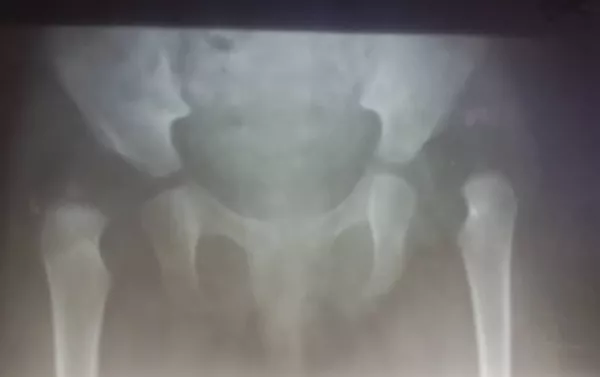

Жамбаштын дисплазиясына кабылгандар ортопедге кайрылышы керек. 1 жана 6 айлыгында УЗИге, 12 айынан баштап рентгенге түшөт. Ошонун жыйынтыгы менен дарылоо жүргүзүлө баштайт.

2-3 айлык балага медицинанын электр тогуна кактап дарылоо (физиолечение — ред.) ыкмасы колдонулат. Адатта наристе 6-8 айлыгында отуруп калса, 9 ай болгондо бир нерсени кармап туруп калат. Бул учурда салмагы менен ныгырылганда бутка күч келип сөөктүн чыгып кетүү коркунучу жаралат. Ошондуктан электр тогуна кактап дарылоодон сырткары сөөктөрдү туура өстүрүү үчүн шакшак коюлат.